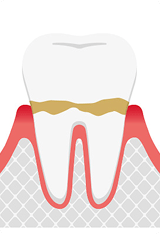

歯肉炎

歯肉炎とは、歯肉溝と言われる歯と歯茎の隙間に磨き残しや汚れが溜まり、細菌が繁殖することで周囲の歯茎が炎症を起こし腫れてしまうことで、ブラッシング時の出血や自然出血が起こる状態を示します。

汚れがこびりついて固まってきますと歯石になります。歯石になってこびりつくと、慢性的に周囲の歯茎が腫れやすくなります。歯肉炎の段階では歯石取りやTBI(歯ブラシ改善)、フロスなどを使用することで改善されます。

軽度歯周炎

歯肉炎が進行して悪化してくると、歯周炎という状態になります。

腫れている歯茎が、深い部分に少し進行した状態です。歯を支えている周辺組織が壊されていく初期段階となります。歯根膜、歯槽骨など歯を支えている組織が歯周病菌の侵入を防ごうとする自己防衛の免疫により破壊されていきます。軽度歯周炎と歯肉炎は、見た目の病態は同じです。

歯肉溝が深くなると歯周ポケットと呼び名が変わります。通常1〜2mmの溝が3〜4mmと少し深くなってくることが特徴です。プロービングといわれる歯周病検査をしないと歯肉炎か歯周炎か判別は難しいです。初期段階であれば、破壊された組織も元に戻る場合もあります。